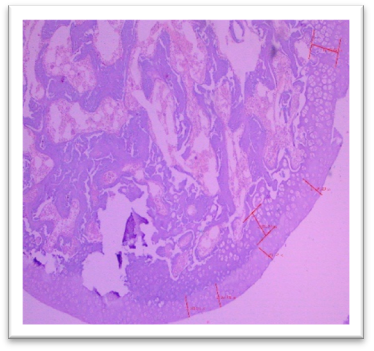

Histomorphometry

At the end of the study, femur bones were dissected and fixed for histological analysis. Group I (Normal) showed normal bone architecture, with well-organized chondrocytes. Group II (Lanthanum Carbonate only) maintained normal bone growth. Group III (Chronic Kidney Disease control) exhibited fibrocartilaginous changes, disorganized collagen, and impaired endochondral ossification, characteristic of Chronic Kidney Dosease. Groups IV (150 mg/kg), V (250 mg/kg), VI (500 mg/kg), and VII (750 mg/kg) demonstrated varying degrees of improvement in bone structure, with the highest dose (Group VII) showing the most significant restoration of normal bone architecture. Histomorphometry of bone: In Group III, designated as positive control for Chronic Kidney Disease, histomorphometric analysis of femur revealed significant fibrocartilaginous changes within the articular cartilage, characterized by an increased fibroblast, loss of chondrocyte organization, and disorganized collagen deposition. Furthermore, the growth plate exhibited a marked increase in the thickness of the hypertrophic zone, suggesting impaired endochondral ossification. Similar findings were observed by Saito et al. (2021) who observed that in Adenine-induced Chronic Kidney Disease, there was a reduction in bone minera density (BMD) throughout the body as well as in the femur Furthermore, micro- computed tomography (micro-CT) analysis revealed a decline in the microstructural integrity of the cortical bone, which contributed to diminished bone strength in both cortical and trabecular regions. Ferrari et al. (2014) reported that the bone microarchitecture in rats subjected to Adenine-induced renal failure exhibited significant alterations, characterized by a reduced trabecular number and an increased trabecular separation. Additionally, the presence of fibrosis was noted in the rats with Adenine-induced renal failure. Ni et al. (2018) performed a histomorphometry analysis and revealing that the bone mineral density (BMD) in the femurs of rats with Chronic Kidney Disease (CKD) was markedly lower than that observed in the control (CTL) group. Additionally, significant bone loss was evident in both cortical and trabecular bone parameters of the femurs.  Lanthanum Carbonate @150mg/kg, 250mg/kg, 500mg/kg and 750 mg/kg, histomorphometric analysis revealed very minimal to nearly absent fibroblast proliferation in the articular cartilage, characterized by the absence of fibroblast- like cells and well-maintained chondrocyte organization. Additionally, the growth plate exhibited moderate proliferation of the hypertrophic zone, indicating significant improvement in endochondral ossification compared to the positive control group (Group III) and lower-dose treatment groups. These findings suggest that the highest dose of Lanthanum Carbonate (750 mg/kg) may provide the most effective therapeutic benefits in mitigating bone-related pathological changes associated with Chronic Kidney Disease Yajima et al. (2018) demonstrated that Lanthanum Carbonate enhanced the mineralization of the periosteal surface, augmented bone mass within the intracortical resorption areas, and improved mineralization on the minimodeling surface at the endocortical region. They concluded that Lanthanum Carbonate has the potential to bolster cortical stability in patients with Chronic Kidney Disease (CKD)..

Fig. 29 Group VI showing minimal fibroblastic changes at articular cartilage and moderate proliferation of hypertrophic zone under H & E 400X.

Fig. 30 Group VII Femur, showed very minimal or nearly absent lesions such as fibroblastic changes at articular cartilage and moderate proliferation of hypertrophic zone under H & E 400X.